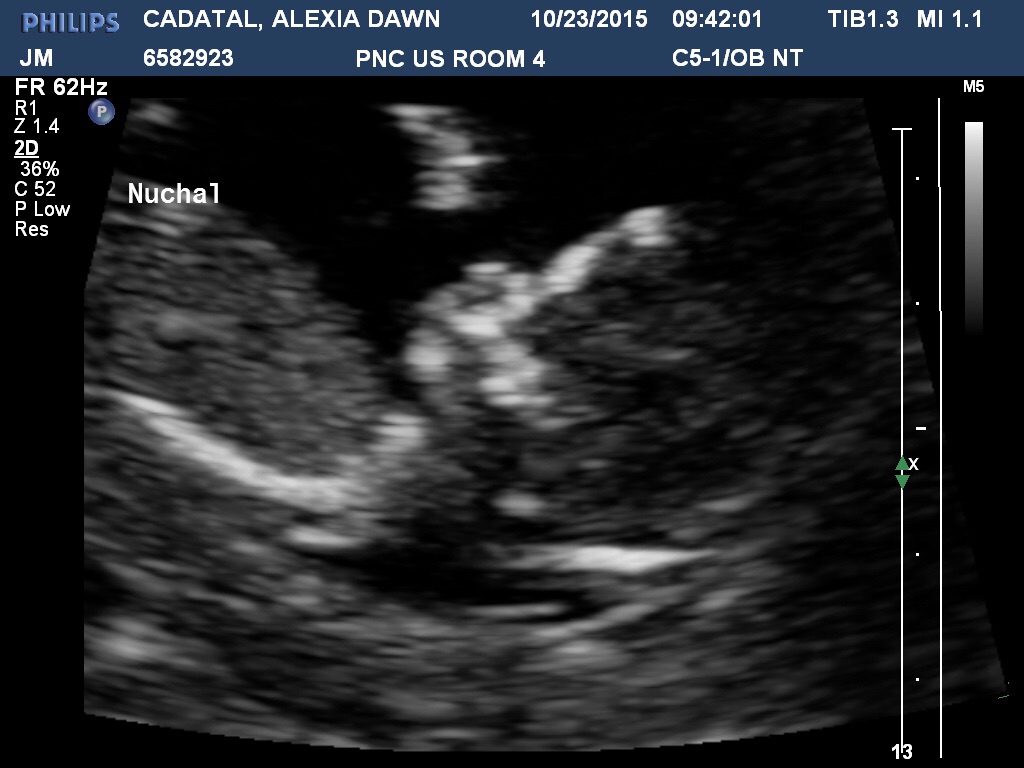

Just had my first US. I have been convinced I am further along than 12 weeks. I ovulate early with a short cycle. Found out I am a full week further along! 13w4d which puts me at April 24th EDD. 144 hb and the US tech kept reassuring me that even though I won't get official results for a week that baby has a very thin measurement for the NT.